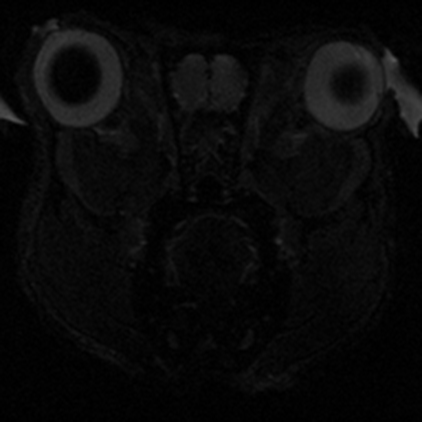

Boğaziçi Üniversitesi Hedefli Tedavi Teknolojileri Merkezi (Boğaziçi CT3) Deney Hayvanları Görüntüleme Birimi, Türkiye’nin ilk preklinik (deney hayvanlarında kullanım için özelleşmiş) 7T MRG (manyetik rezonans görüntüleme) cihazının yanı sıra preklinik BT (bilgisayarlı tomografi) ve hem MRG hem de BT tarayıcıları ile entegre edilerek PET-MRG ve PET-BT çalışmalarına olanak tanıyan PET tarayıcısı ile araştırmacılara ve sektördeki kuruluşlara eşsiz bir altyapı sunmaktadır.

Birimimizde; tüm vücut ve bölgesel MR taramaları, doku karakterizasyonu, metabolik görüntüleme, moleküler hedeflerin izlenmesi ve farmakokinetik değerlendirmeler gerçekleştirilebilmektedir. Ayrıca hayvan kabul ve karantina alanlarımız, uluslararası etik standartlara uygun olarak yapılandırılmıştır.

Yüksek alan kuvveti sayesinde sağlanan üstün görüntü kalitesi ve hassasiyet, özellikle onkoloji, nörobilim, kardiyovasküler ve farmasötik araştırmalarda büyük avantajlar sağlamaktadır. Araştırmalarınıza özgü deneysel protokoller geliştirme, planlama ve analiz süreçlerinde, deneyimli teknik ekibimizle kapsamlı destek sunuyoruz.